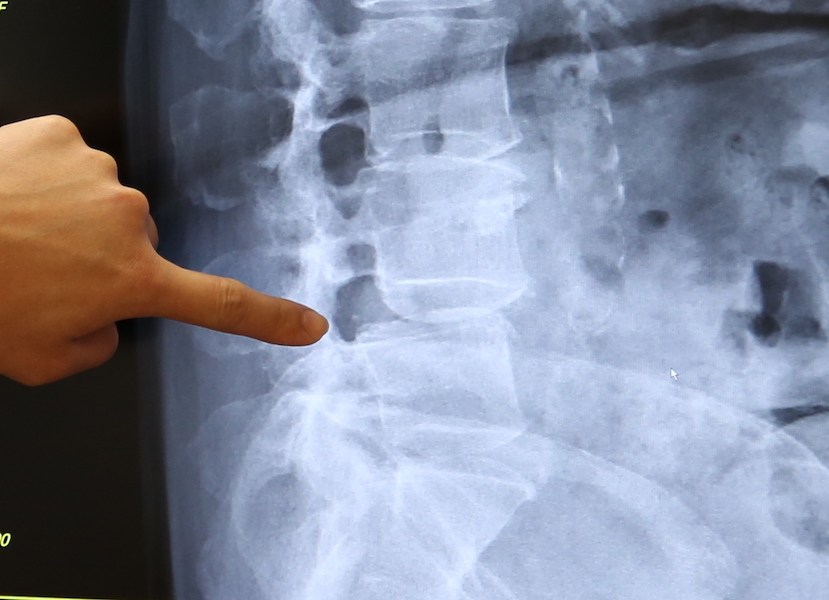

於是在兒女建議下,林太太到花蓮做手術治療。一經磁振造影檢查,發現林太太是腰椎滑脫。

林太太的下背及坐骨神經痛原來是脊椎滑脫所致,經微創腰椎融合手術後,隔天即可下床行走。

脊椎原是圓柱狀的椎體,一節接着一節,原本椎體後緣是要對齊的,但是卻出現明顯的錯位,就是滑脫。如果林太太當時的滑脫程度去做復健治療,拉腰牽引的過程,只會讓病人滑脫的關節更不穩定,這也是為什麼林太太復健之後,不但沒有好轉,反而更痛的主要原因。而透過微創腰椎融合手術,挽救被壓迫的神經,重建退化不穩定的脊椎。林太太隔天就可以下床行走。

脊椎原是圓柱狀的椎體,一節接着一節,椎體後緣是要對齊的,若出現明顯的錯位,就是滑脫。